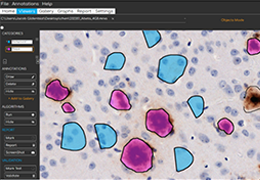

ART-Plan™ Artificial Intelligence Contouring